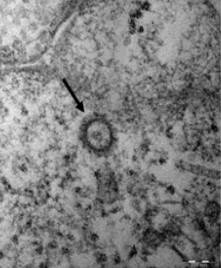

전문가들 사이에서는 이번 코로나19의 확산이 사스와 비슷한 양상을 보일 것이란 예측을 내놓는다. 코로나19와 사스는 같은 베타코로나바이러스 계열로 유전적 유사성이 80% 정도 일치하고 겨울철 감염병이란 공통점을 가지고 있기 때문이다.